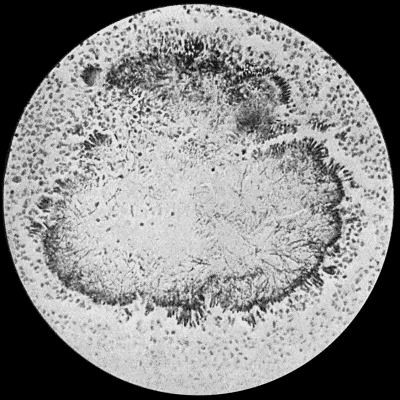

122 30.Colony of Actinomyces

Fig. 2.—Staphylococcus aureus in Pus from case of Osteomyelitis. × 1000 diam. Gram's stain.

Staphylococcus Aureus.—This is the commonest organism found in localised inflammatory and suppurative conditions. It varies greatly in its virulence, and is found in such widely different conditions as skin pustules, boils, carbuncles, and some acute inflammations of bone. As seen by the microscope it occurs in grape-like clusters, fission of the individual cells taking place irregularly (Fig. 2). When grown in artificial media, the colonies assume an orange-yellow colour—hence the name aureus. It is of high vitality and resists more prolonged exposure to high temperatures than most non-sporing bacteria. It is capable of lying latent in the tissues for long periods, for example, in the marrow of long bones, and of again becoming active and causing a fresh outbreak of suppuration. This organism is widely distributed: it is found on the skin, in the mouth, and in other situations in the body, and as it is present in the dust of the air and on all objects upon which dust has settled, it is a continual source of infection unless means are taken to exclude it from wounds.